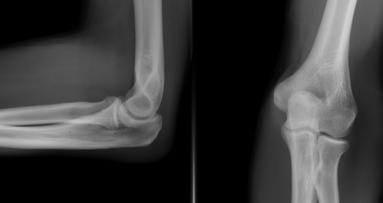

Autorzy wynalazku zwracają uwagę, że w ostatnich 40 latach liczba zapaleń kości i szpiku wzrosła trzykrotnie. Jednocześnie, jak wyjaśniają, zmiany martwicze powstające w wyniku infekcji kości można dostrzec w badaniu rtg dopiero, gdy 50-75% macierzy kostnej ulegnie zniszczeniu.